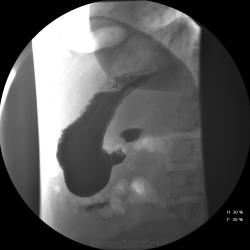

Женищина 49 лет, повышенного питания, обратилась с жалобами на потерю аппетита, жжение после чуть острой пищи, отрыжку с неприятным запахом, иногда темный стул, несколько похудела. Данные жалобы с сентебря-октября. Никуда не обращалась, коррегировала питанием. В последнее время стало хуже, обратилась...

Привратник удлиннен и ригиден, такое бывает при раке. Рек. ЭГДС.

Вы правы. я несколько недорасказал. женщина пришла уже с фгдс - инфильтративно-язвенный процесс в выходном отеде желудка у привратника по малой кривизне с переходом на переднюю стенку. так что прицельно смотрел этот отдел. перистальтка была ослаблена, краевой дефект в препилорической зоне по малой кривизне, передней стенке, кажущееся удлинение привратника, нависание основания луковицы - вообщем как в книжке. эвакуация было не изменена. написал рак выходного отдела желудка. вчера пришла гистология - высокодиф-я аденокарцинома. вот такая история.

Пока, касаясь только луковицы, но не препилорического отдела. "Ниши" в луковице есть, и они нуждаются в объяснении.

Конечно, в пилорическом канале уже растет, и "это" растет, уже и препилорической части и в луковице 12-ти перстной кишки.

Снимки забираем в набор изображений, очень показательные.

И, рельф атипичный.